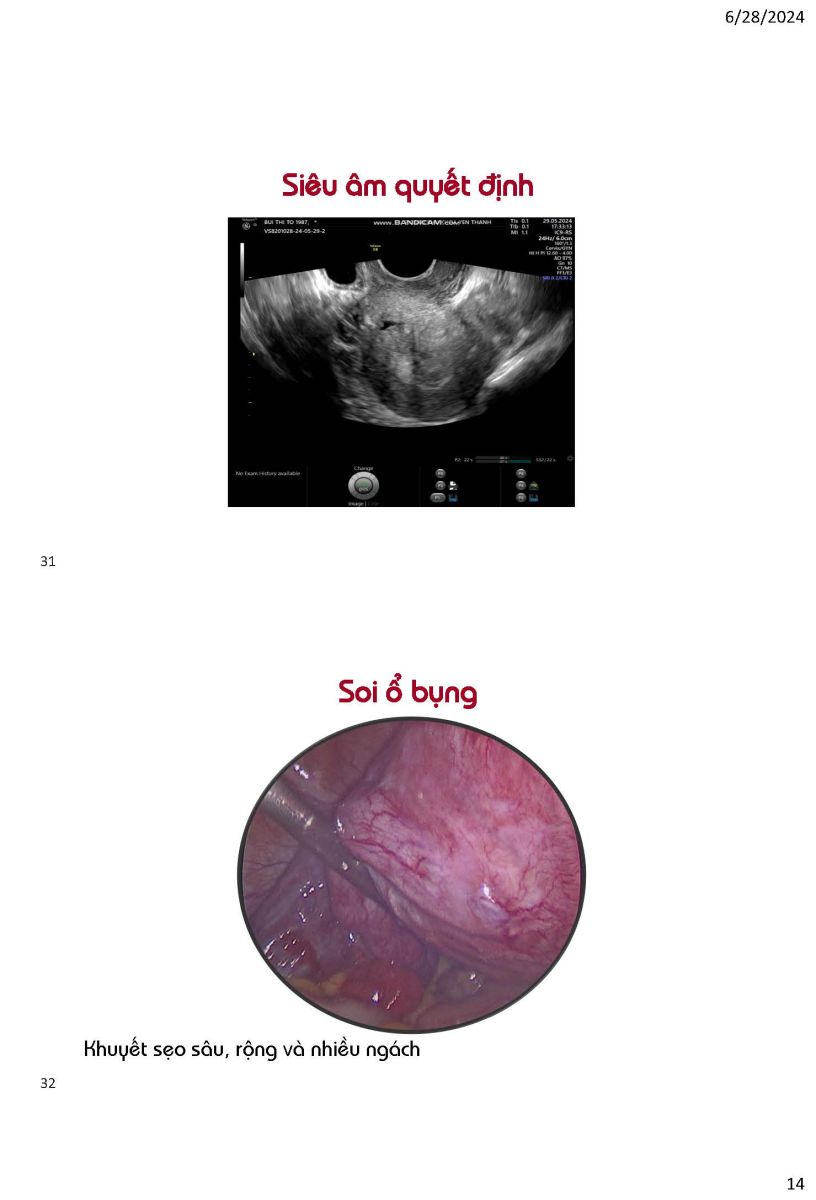

Ứng dụng siêu âm trong quyết định phương pháp can thiệp khuyết sẹo mổ lấy thai